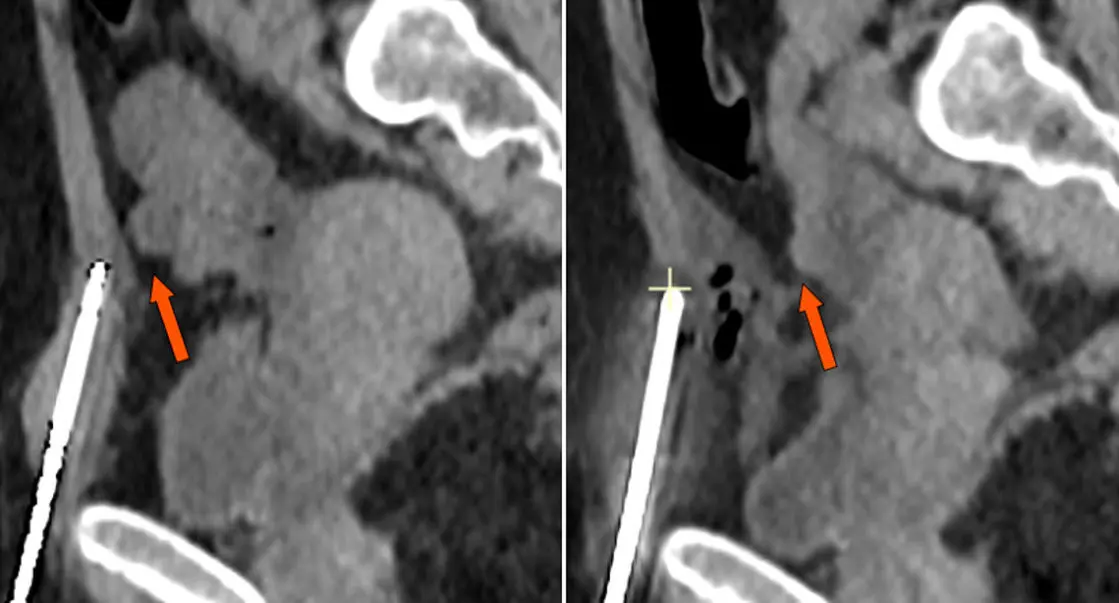

d’endométriose pariétale du muscle grand droit. Coupe sagittale passant par l’aiguille de cryoablation en place avant (à gauche) puis après hydrodissection (à droite)

L’hydrodissection a permis d’éloigner l’anse grêle (flèche) située initialement à proximité immédiate du bout de l’aiguille en place. Le glaçon (croix jaune, en cours de formation sur l’image de droite), ne sera ainsi pas en contact avec l’anse grêle et le traitement peut se faire en toute sécurité.